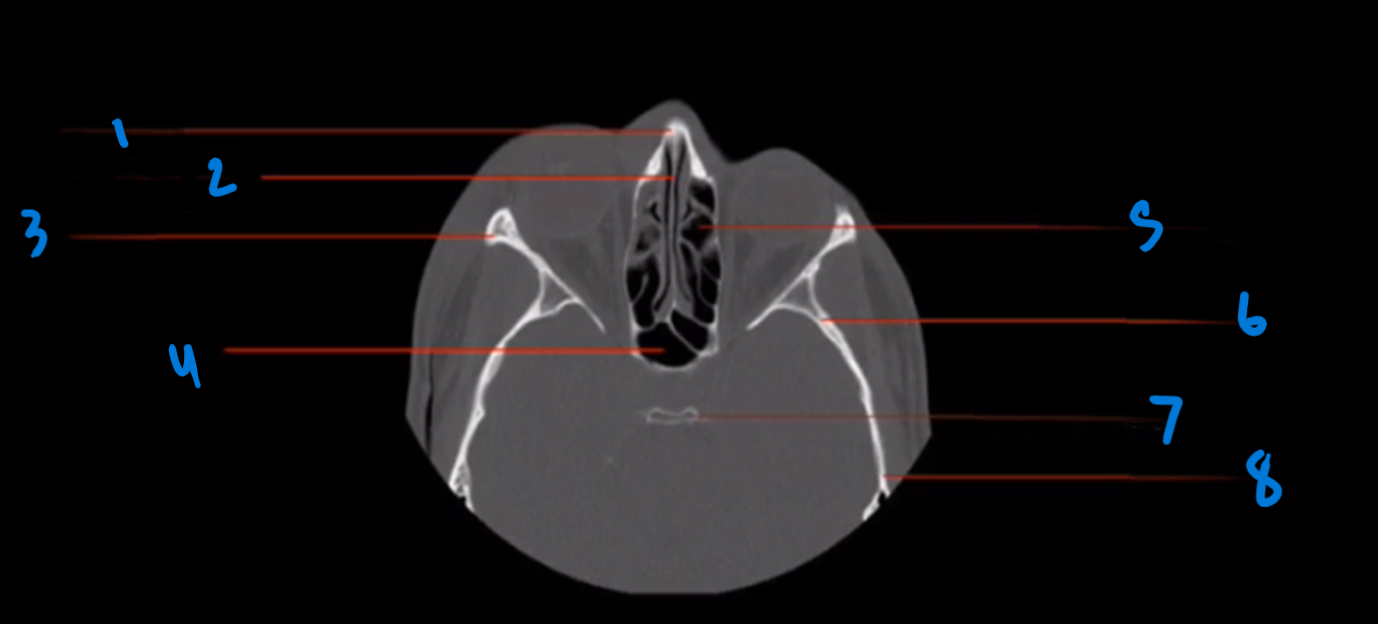

Landmark 1?

Maxillary Bone

Landmark # 2

Maxillary sinus

Landmark #3?

Coronoid process, mandible

Landmark # 4 called?

Mandibular condyle

Landmark # 5?

Carotid Canal

Landmark # 6?

Jugular Foramen

Landmark # 7?

Nasal Septum

Landmark # 8

Nasolacrimal duct

Landmark # 9

Zygoma

Landmark # 10

Zygomatic arch

Landmark # 11?

Clivus

Landmark # 12

External Auditory Meatus

Landmark # 13

Mastoid Air Cells, Temporal Bone